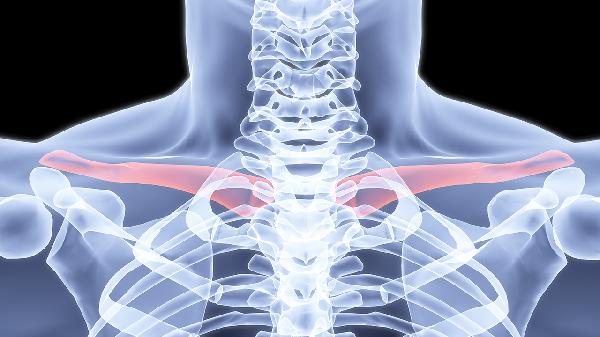

右边锁骨下面骨头突出怎么回事

右边锁骨下面骨头突出可能与锁骨骨折、肋软骨炎、骨肿瘤、胸锁关节脱位、先天性发育异常等因素有关。右边锁骨下面骨头突出可通过影像学检查、药物治疗、手术治疗等方式干预。